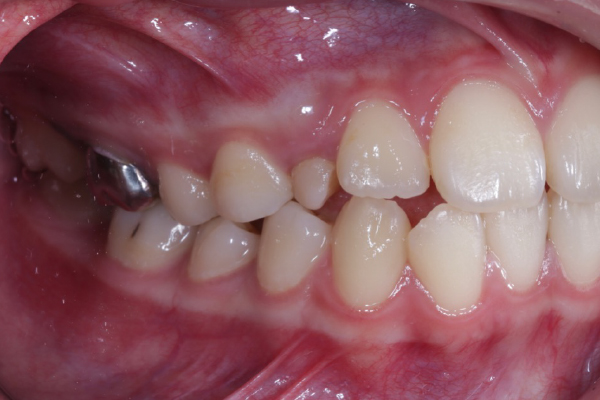

BEFORE

前歯で物を咬めない、見た目を治したいということで来院されました。前歯は咬んでおらず奥歯しか当たらない状態でした。咬み合わせが不安定でどこで咬んでいいかわからないということでした。小臼歯抜歯を行いワイヤー矯正にて治療を行うことになりました。